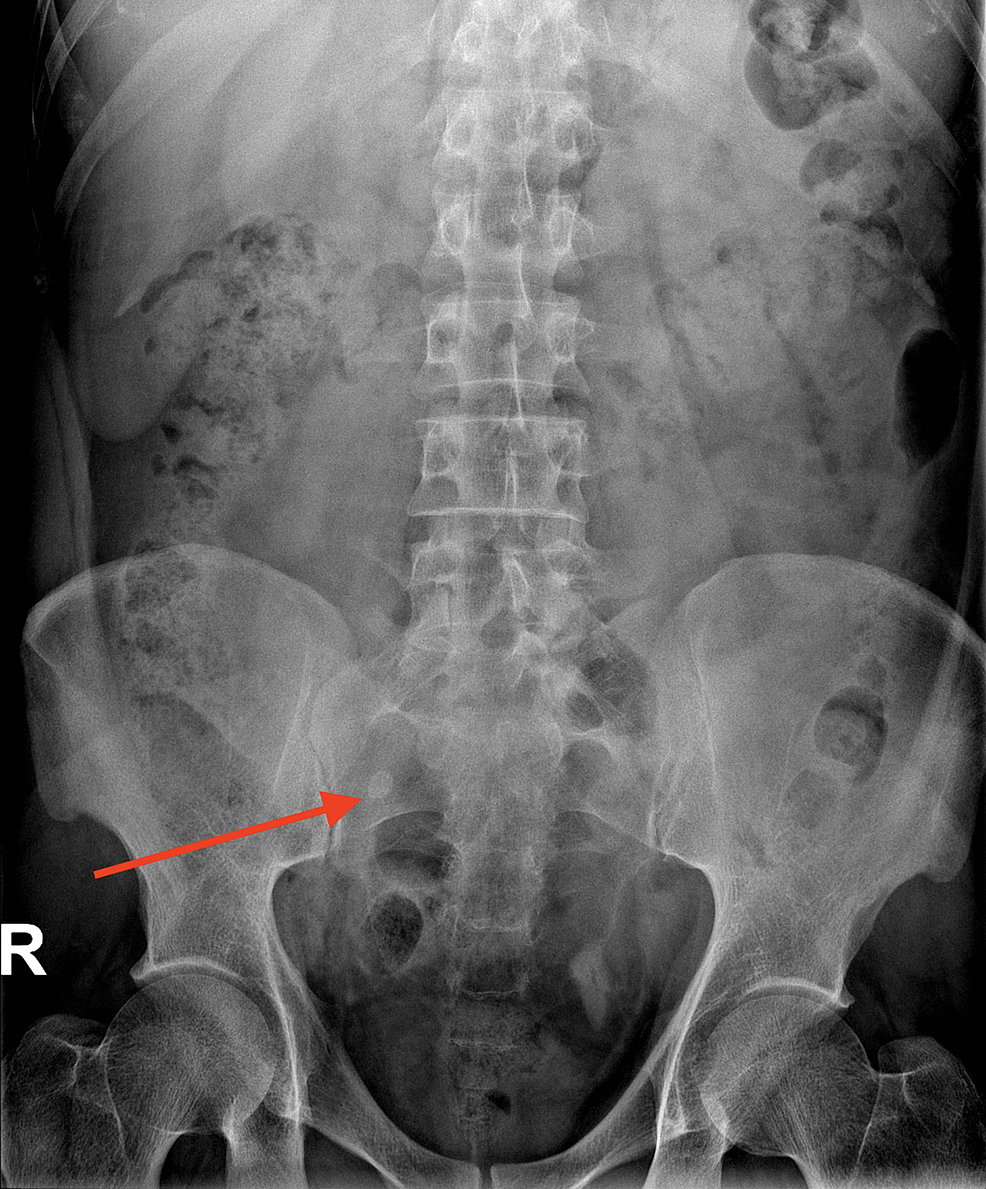

Axial CT of a fluidfilled drain tract (arrow) mimics stump What Is The Appendicular Stump   stump appendicitis is a real and likely underreported disease process in.   stump appendicitis is a rare, delayed complication of appendectomy.   stump appendicitis is a rare etiology of abdominal pain, often.   stump appendicitis results from obstruction of the lumen of the remaining appendix stump, usually by a faecolith.   closure of the appendiceal stump is a key. What Is The Appendicular Stump.

From link.springer.com